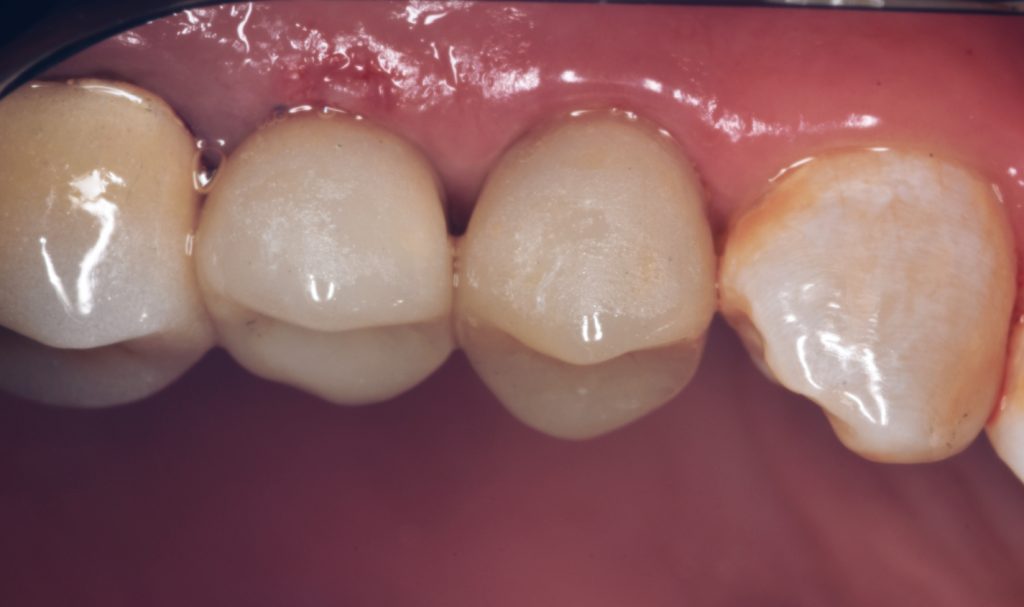

I decided to go for indirect lithium disilicate restorations

And final design to receive to monolithic lithium disilicate restorations

Cementation by heated composite

Shofu beautifill LS